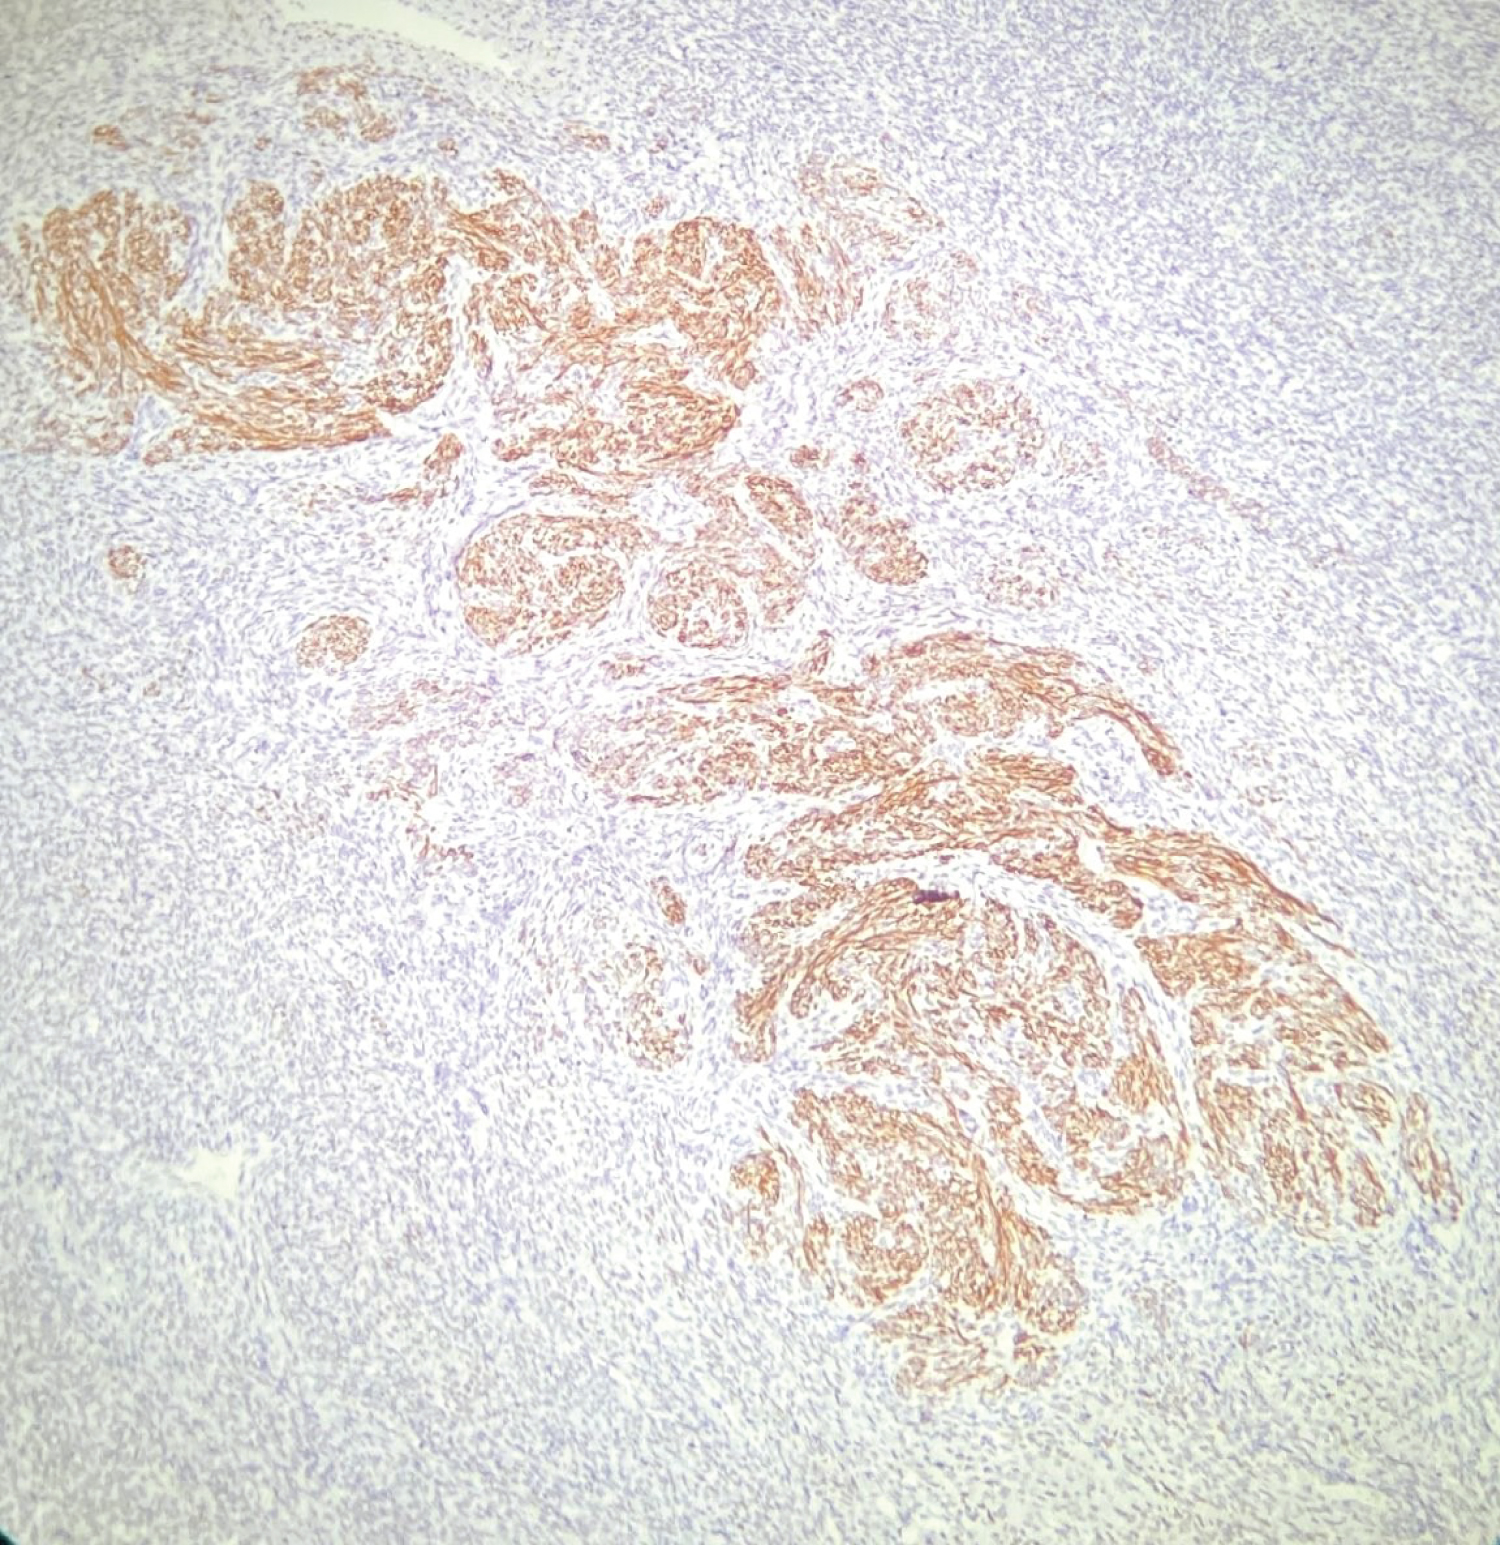

Histomorphological findings showed that nodule has a non-infiltrative border and consists of uniform small cells with oval-round, blue, basophilic nucleus with chromatin which is finely granular, has an indeterminate nucleolus, and a scant cytoplasm (Figure 1 and Figure 2). Tumor cells expressed diffuse CD10 and weakly SMA positivity (Figure 3).

Figure 3: CD10 shows mostly positivity in uniform cells and negativity on the center which displays smooth muscle differentiation called starburst morphology (× 200, CD10). View Figure 3

The lesion was in cellular morphology and there was no cellular atypia, mitosis or necrosis. Hyalinized smooth muscle differentiation which expressed desmin and caldesmon (Figure 4 and Figure 5) and MTK positivity showing starburst morphology was observed in the focal areas (Figure 6). Starburst pattern is composed of smooth muscle differentiation with central hyalinisation and radiating collagen bants at the periphery encircle round cells (Figure 2). There was no lymphatic, vascular or myometrial invasion.

Differential diagnosis of endometrial stromal nodules completely depends on the histopathological findings. Multiple preparate examination and serial cut sections must be performed. These stromal nodules have expansile, non-infiltrative margins with adjacent myometrium [7]. Lymphatic and vascular invasion is absent. Immunhistochemical expression includes CD10 positivity, SMA, caldesmon and desmine negativity (or weakly positivity).

In our case, the tumor expresses diffuse CD10. Only starburst pattern showed Desmin and Caldesmon positivity. The nodule was immunonegative with desmine and caldesmon in the regions other than these starburst areas.